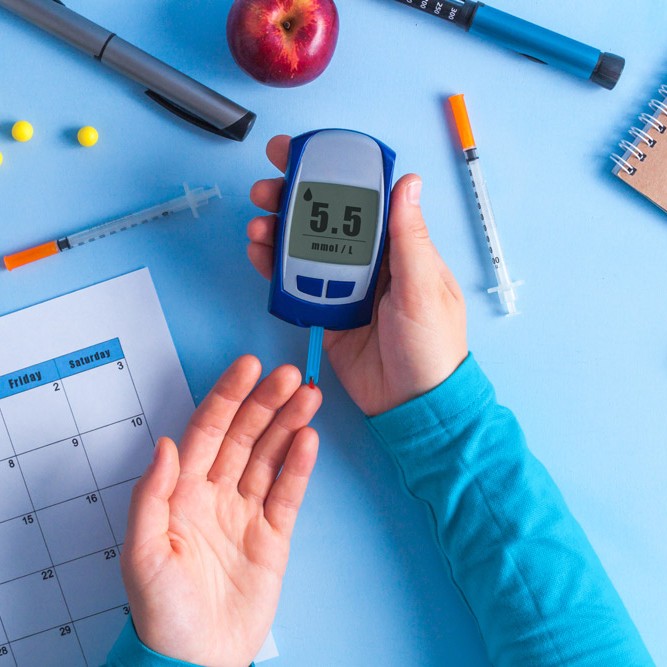

Diabetes

- Uncontrolled blood sugar increases the risk of gum disease.

- Reduced saliva in diabetic patients leads to less protection against bacteria and plaque.

- Higher glucose levels in saliva promote bacterial growth.

- Diabetes care and dental care are closely linked.

- Even if you do not have diabetes, studies have shown inflammation caused by gum disease increases your risk for diabetes.